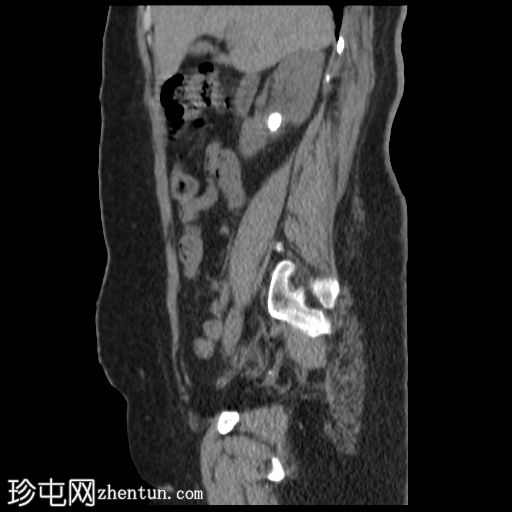

轴位

平扫

平扫CT显示右肾盂内有一结石,大小约17 × 16 mm,CT值1115 HU,引起轻度肾积水。右肾下盏内可见另一小结石,大小约8 × 4 mm,CT值611 HU。

子宫前壁可见一软组织肿块,大小29 × 24 mm,与子宫肌层密度相近,呈外生性生长,无钙化或脂肪成分。

其他腹部器官CT检查结果正常。

非增强 CT 对检测泌尿系统结石具有很高的敏感性。大多数结石为放射性不透光结石,其衰减值因成分而异。本例中,较大的右肾盂结石的衰减值为 1115 HU,符合鸟粪石的特征,鸟粪石通常与感染有关,在女性中更为常见,并且可能形成鹿角状结石。

较小的下肾盏结石的衰减值为 611 HU,提示为草酸钙结石。识别结石成分对于指导治疗和预防具有重要的临床意义。

关于子宫病变,其主要符合浆膜下肌瘤的特征。建议进行经阴道超声检查。